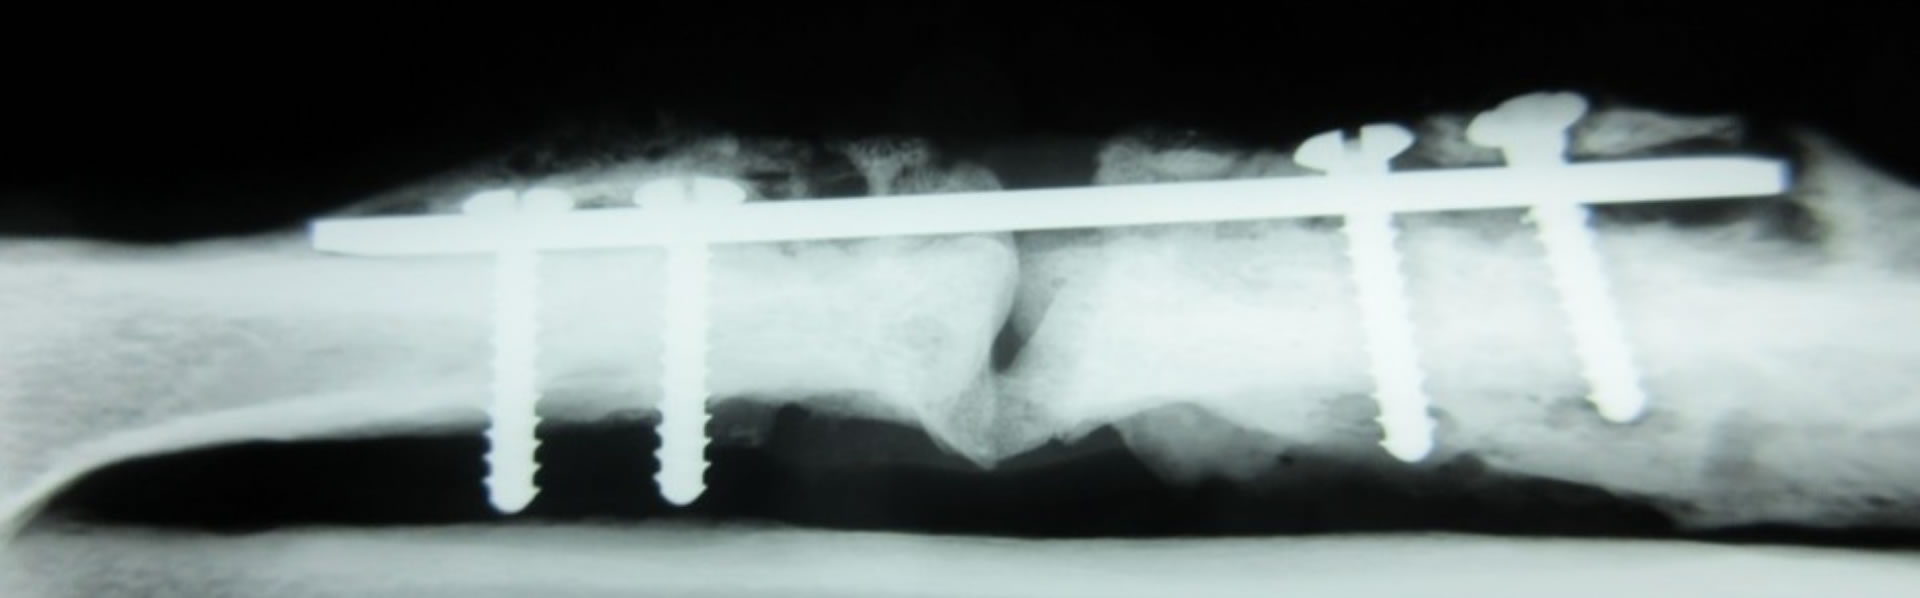

Our research focuses on metal-based crystalline materials. We aim to systematize materials design methods for advanced control of material properties that emerge from static and dynamic changes in atomic arrangements and microstructures. Through this approach, we pursue the development of new materials and the proposal of innovative processing techniques. In addition, we strive to accurately identify challenges and needs in clinical settings and work toward creating metal-based medical devices that provide functions tailored to those needs.